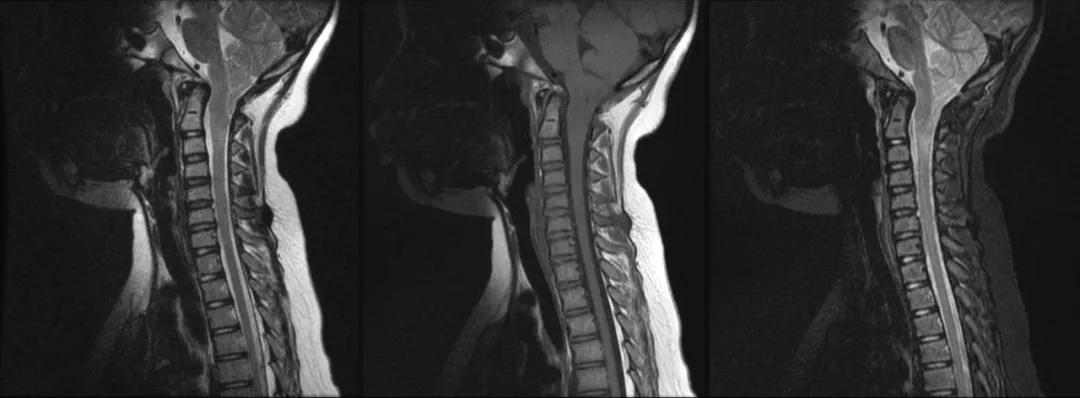

case 1:男性 ,14 岁,头颈部疼痛、不适 1 年

诊断:Chiari 畸形 I 型

case 2:女性 ,56 岁,右侧肢体感觉障碍,肌萎缩 2 年余

诊断:Chiari 畸形 I 型合并脊髓空洞症。